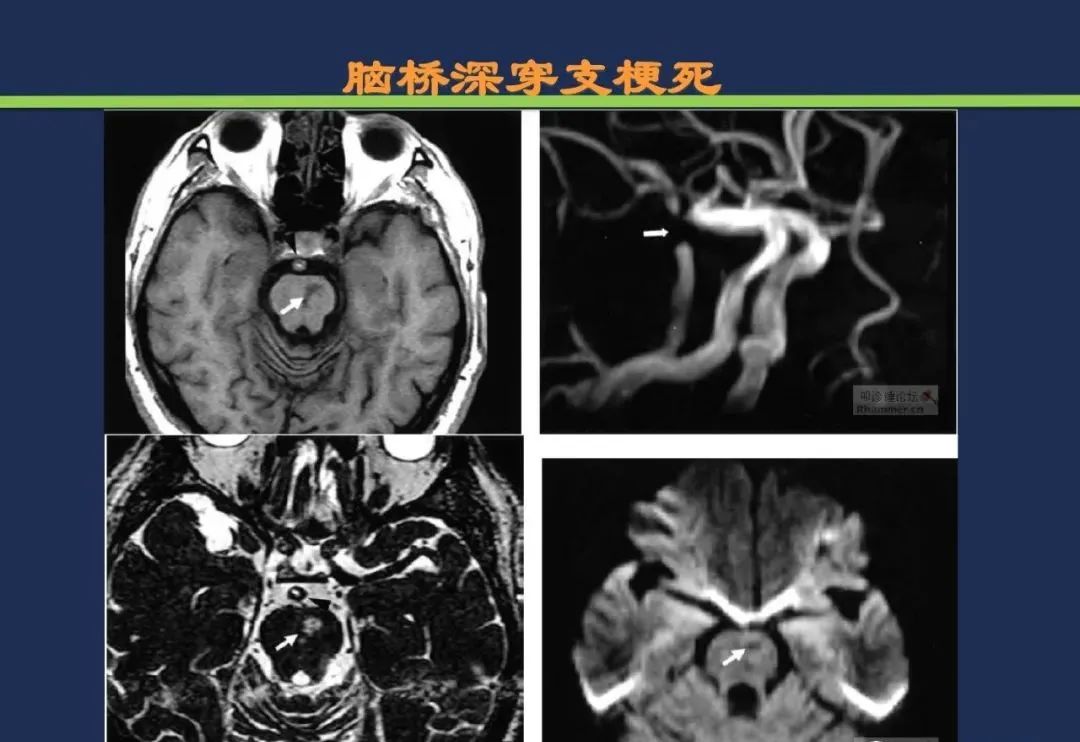

脑桥旁正中动脉